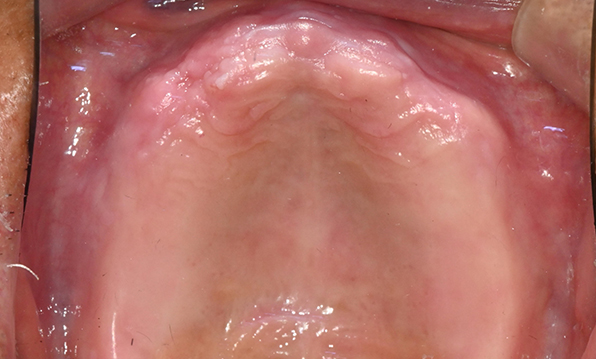

Before & After

| Before | After |